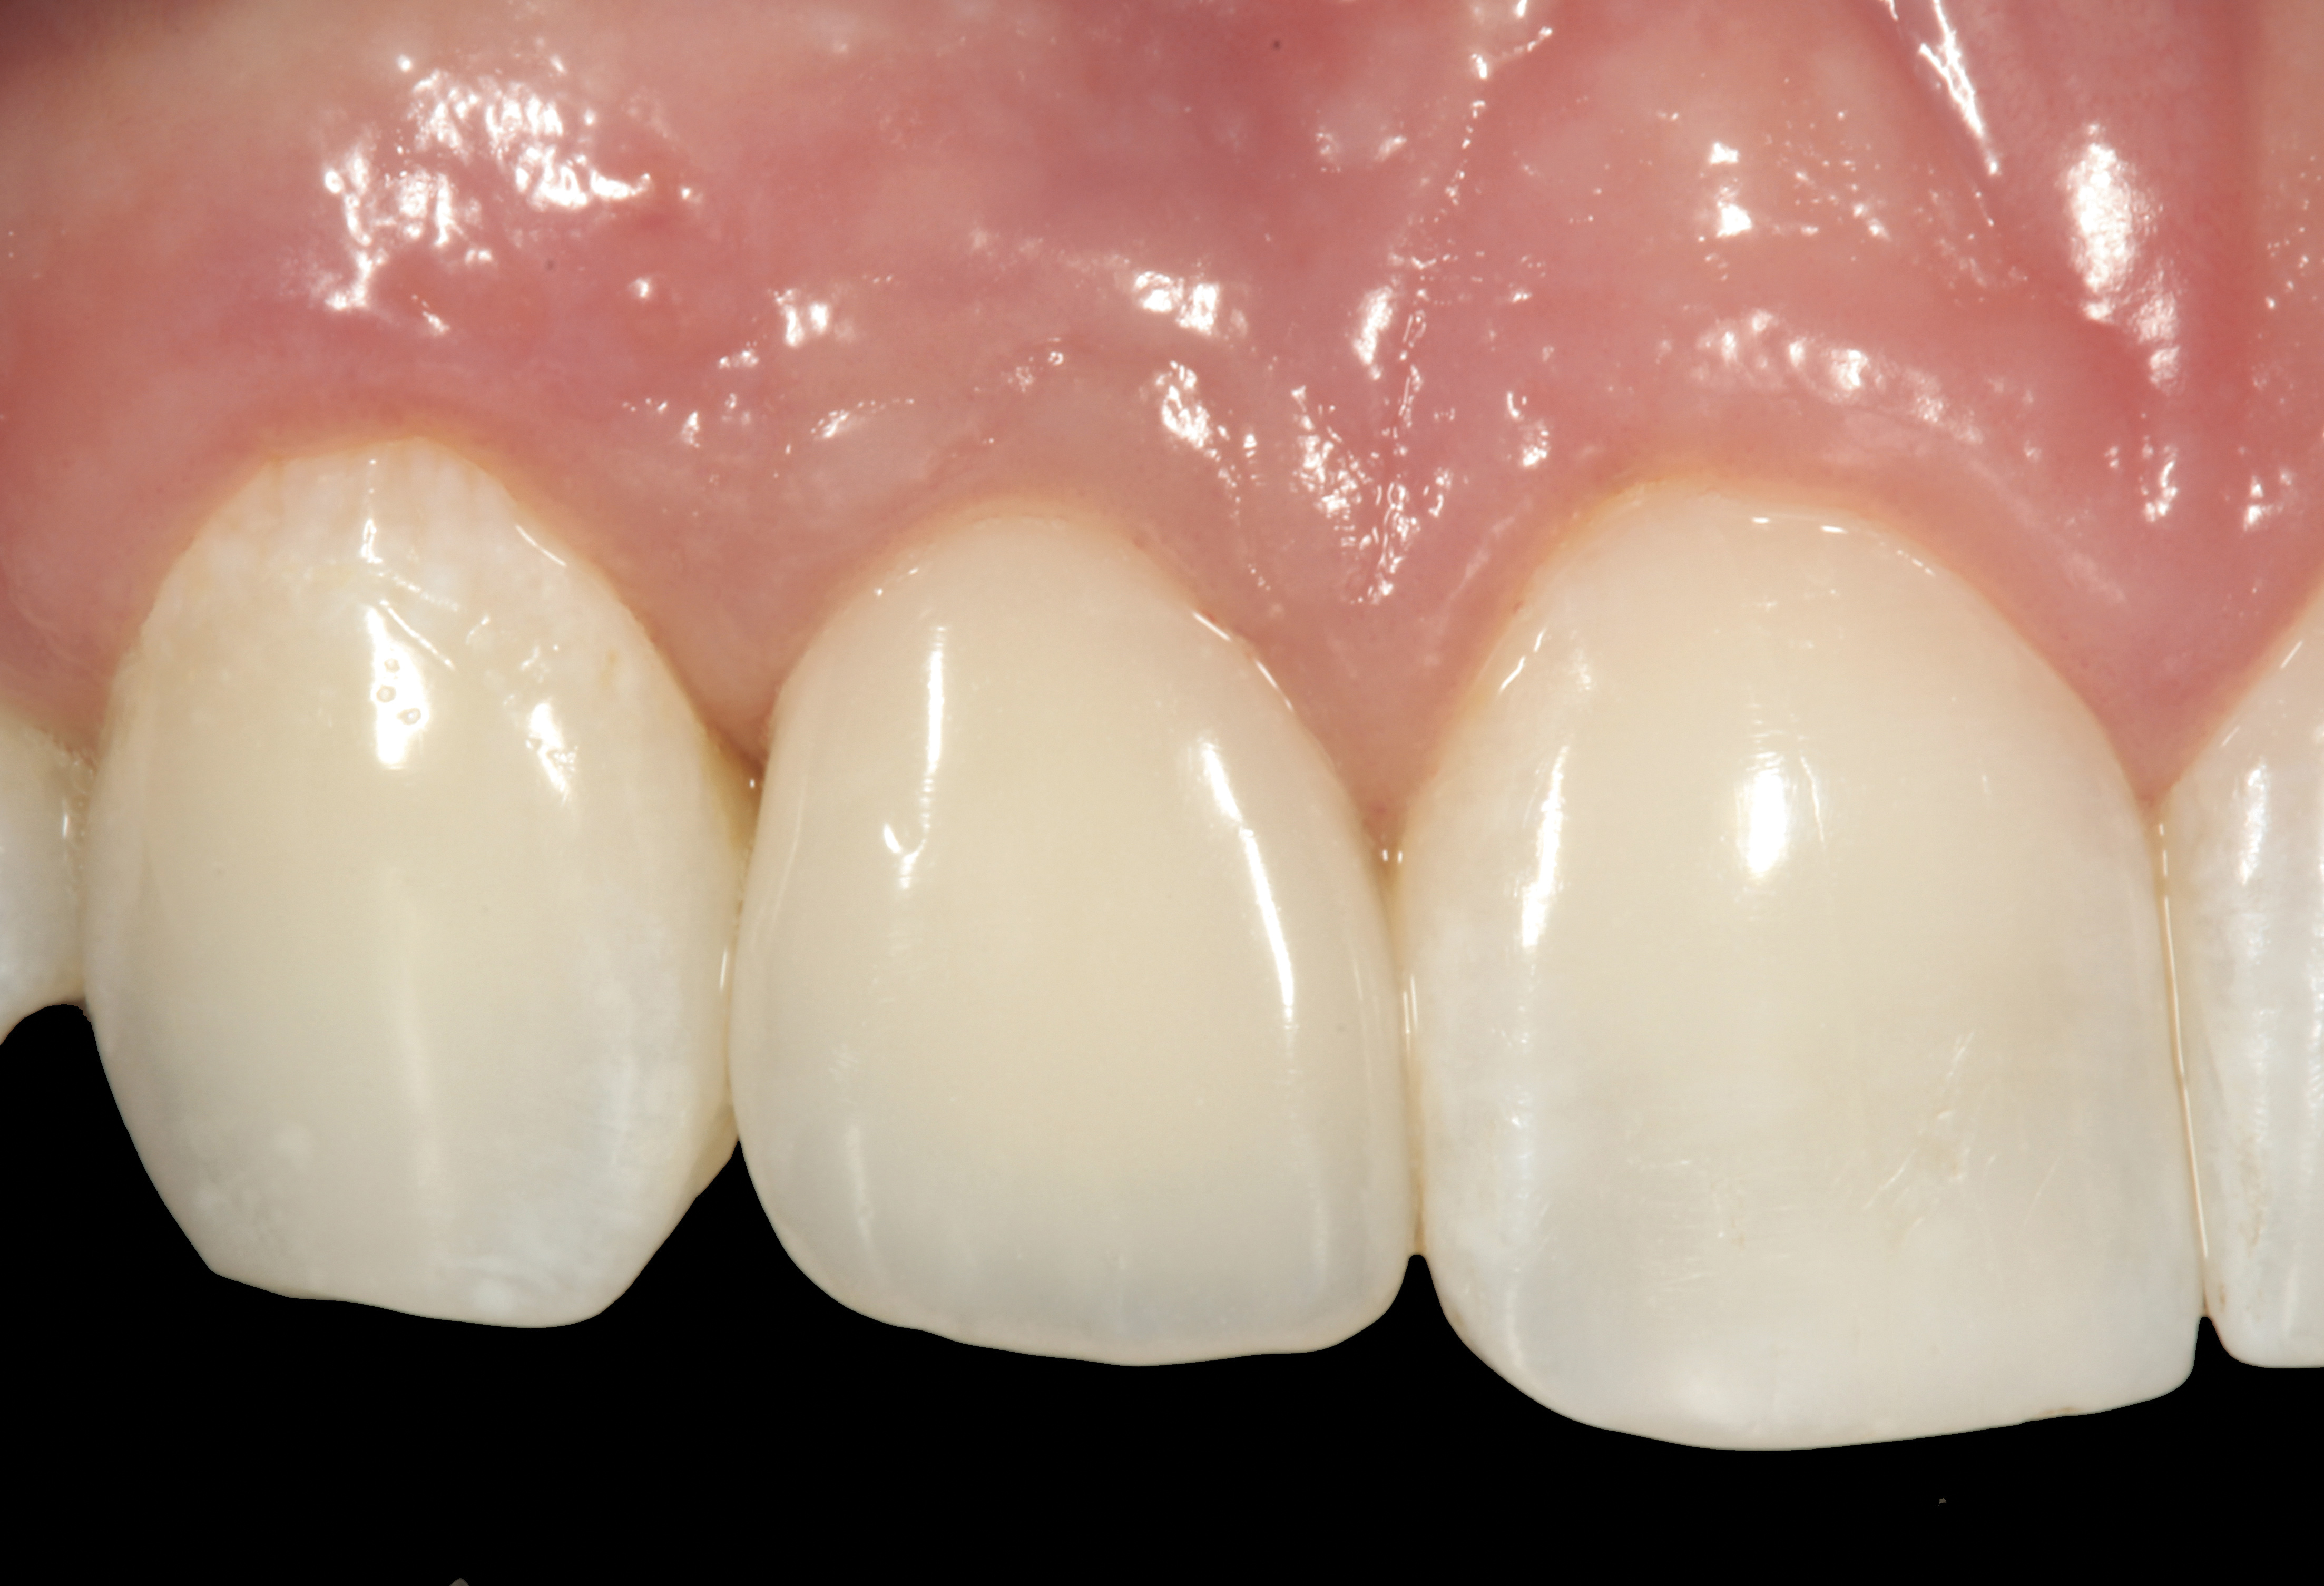

It was determined that additional augmentation was required to increase the soft-tissue volume, so a subepithelial connective tissue graft was acquired from the palate (Figure 8),23,24 placed, and allowed to mature for at least 3 months. Second-stage implant undercovering surgery with a palatal-biased incision was performed after tissue maturation to further thicken the labial soft tissues. In addition, a flat contoured healing abutment was placed to allow the soft tissues to mature without risk of recession, and the RBR replaced (Figure 9). After 4 to 6 weeks of healing, a flat contoured screw-retained provisional restoration was inserted (Figure 10) with the proper submergence profile to restoratively sculpt the soft tissues. An implant-level impression was made and the definitive cement-retained metal-ceramic restoration fabricated and inserted (Figure 11 through Figure 13). The final esthetic outcome to restore the proper length and proportion of the right lateral incisor to match that of the contralateral incisor was accomplished using the treatment steps outlined above, where the mucosal tissues were augmented after implant decoronation (Figure 14).

Fig 9. After 3 months of healing, the implant was uncovered. A crestal incision was made with a palatal bias and rolled to the labial side to increase the soft tissue to the facial aspect.

Figure 9

Fig 10. A flat submergence profile was created for the screw-retained provisional crown. Acrylic resin was strategically added to the cervical aspect of the provisional restoration to accomplish this goal.

Figure 10